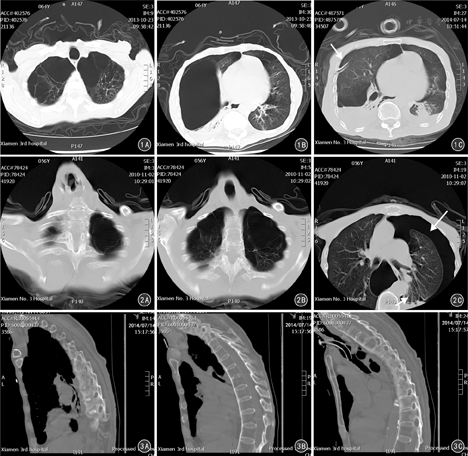

8例均表现为尖纤维化,肺尖部容积明显减少,双肺均可见巨大型肺大疱(图1),5例位于双肺中上肺野,3例双肺上、下肺野均有分布。其中5例出现肺大疱破裂并发气胸,右侧3例(图1),左侧2例。患者颈椎和胸椎生理曲度变直(图2);矢状位多平面3D重建胸部HRCT显示,椎体增生呈"竹节样"改变,小关节突明显增生,关节间隙变窄或融合消失(图3)。

患者中下肺野未合并感染时主要表现为网格影,小叶间隔增厚;合并感染时主要表现为双下肺的实变不张及支气管管腔内的粘液栓嵌顿。双侧胸膜均增厚,双侧胸腔少量积液,合并心衰、肾功能衰竭和/或低蛋白2例,此时胸腔积液量呈中等量。8例患者胸部HRCT表现及分布见表3。

AS并发肺损害在胸部HRCT的表现因其病程的阶段不同也不一样。在AS病程的早期就可以引起肺尖纤维化,初以右上肺区多见,双肺出现小结节;随着病情的进展结节可发生融合成为较大的阴影;晚期可形成空洞和囊腔,肺实质的纤维化和胸膜病变。胸部HRCT较普通CT更加敏感,有助于发现AS患者肺部病变的范围、肺实质纤维化、肺容积改变、空洞形成、支气管扩张和胸膜增厚。尤其是对胸部HRCT的矢状位3D成像更能发现AS患者胸椎及脊柱的典型病变特征:胸椎生理曲度变直及椎体呈"竹节样"增生。

本研究中8例AS并发肺大疱、气胸均发生于AS病程的后期(均有AS病史20~40年),这与文献报道基本一致[9,10,11]。8例患者胸部HRCT均提示有双肺尖纤维化及双肺多发巨大型肺大疱,最大者可占据整个肺叶。因此,对于肺部影像学表现为肺大疱、气胸的患者需要警惕AS。临床上,COPD患者胸部HRCT也可变现为肺大疱、气胸,尤其是老年男性,很容易被误诊AECOPD并发气胸,这也是本文8例就有5例被误诊AECOPD并发气胸的主要原因。但仔细观察可发现COPD的胸部HRCT同时有肺气肿、桶状胸、肋间隙增宽的表现,而AS则是胸廓硬变,HRCT的矢状位成像就更易发现COPD患者的胸椎没有生理曲度变直及椎体呈竹节样增生的表现。